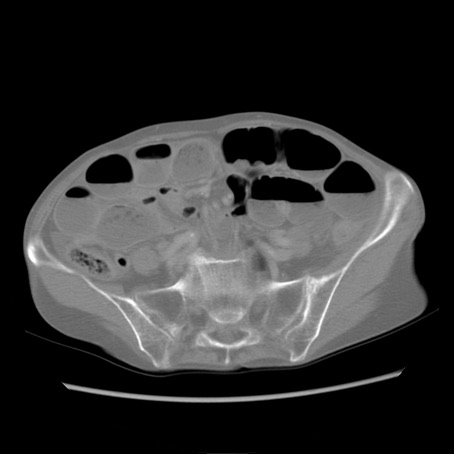

症例25(横断像)

症例

【症例】80歳代女性

【主訴】胸のつかえ感

【現病歴】約9時間前に食後から胸のつかえた感じあり、嘔吐あり、来院。

【既往歴】胃癌(全摘)、胆摘、虫垂炎

【身体所見】心窩部に圧痛あり、反跳痛なし。

【データ】WBC 5700、CRP 0.05